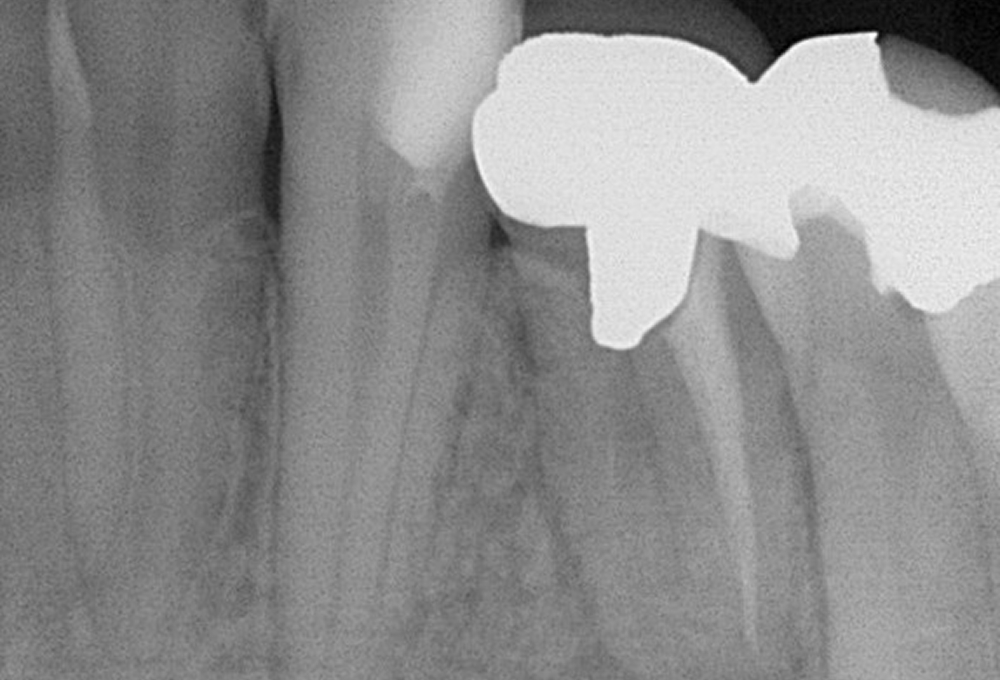

①術前 歯冠大の根尖病変